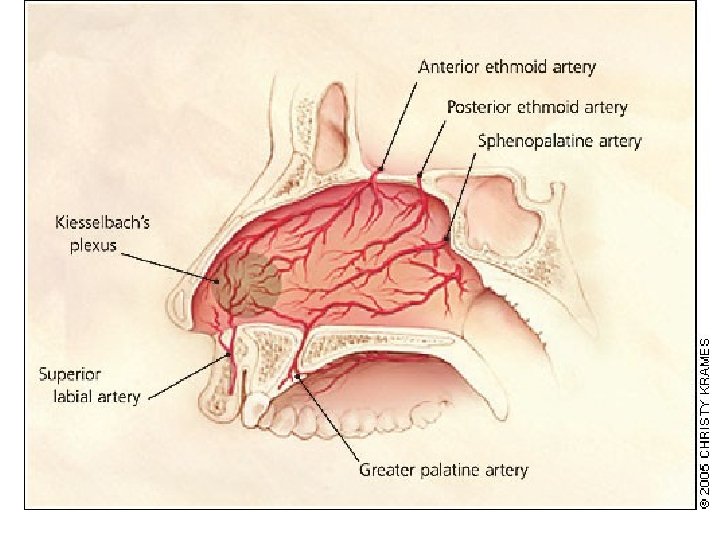

• Blood supply: facial and ophthalmic arteries and veins • Lymphatic drainage: preauricular and submandibular lymph nodes

• Trigeminal nerve carries the common sensation via ophthalmic and maxillary divisions. • Special sensory (smell) carried via olfactory nerves.